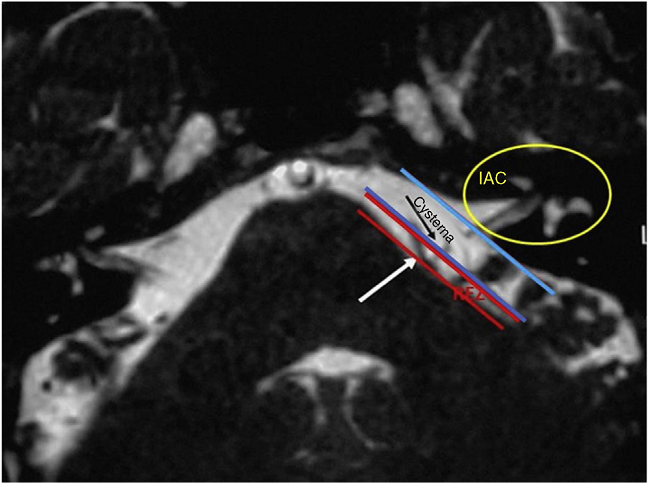

The diagnosis of HFS was performed on the basis of subjects' clinical history and radiological imaging. Magnetic Resonance Imaging (MRI) or angio MRI8-11 using T1 and T2 sequences were made on all patients to rule out other cranial neuropathies of the cerebellopontine angle (CPA). MRI T2 sequence is the most sensitive in identifying the vessels impinging the facial nerve8-24 in the CPA root exit zone (REZ) and more rarely in the entry of the porus. All patients signed a written informed consent.

In our study, all patients (100% of cases) presented a correlation between diagnosis and surgical finding.Among our patients, we observed a predominance of left side NVCs (8/12 subjects) with a more frequent involvement (51% vs. 25%) of the posterior-inferior cerebellar artery (PICA) than the anterior-inferior cerebellar artery (AICA). In 2 cases a multiple PICA-vertebral artery impingement on the facial nerve was noticed. The basilar and the vertebral arteries were responsible for the MVC in 1 case each (Fig. 3). An arterial loop impinging the facial nerve was found jutting into the entry of acoustic porous in 33% (4/12 patients) of cases and, involving REZ area only, in 69% (7/12) of subjects (Fig. 4), with significant statistically result (p < 0.05). Only one patient affected from HFS with negative MRI for MVC, we identified a vein crossing the facial nerve. The vein was intracanalicular and in contact with pons. Our patients reported a previous clinical history of HFS average presence of 10 years (SD = 7.1; 95% CI 2-29) at the moment of surgery and 66% of them had undergone previous BoTN treatment.

In our study, a constant association between HFS side and NVC site was noticed, which confirms the concept that a contact between a vessel loop and the facial nerve is responsible for facial spasm (Fig. 6). Nevertheless no significant difference was observed in our sample in the site of nerve compression (REZ vs. IAC), we recorded a higher frequency of porus involvement (33%) with respect to other authors,2,8-10 The use of combined approach offers a better vision of the course of the offending vessel due to the endoscope view that allows to investigate the vessel position at 360°. The use of a 30° endoscope allowed us a better "around-the-corner" visualization of the IAC in contrast to the microscope's straight linear view.